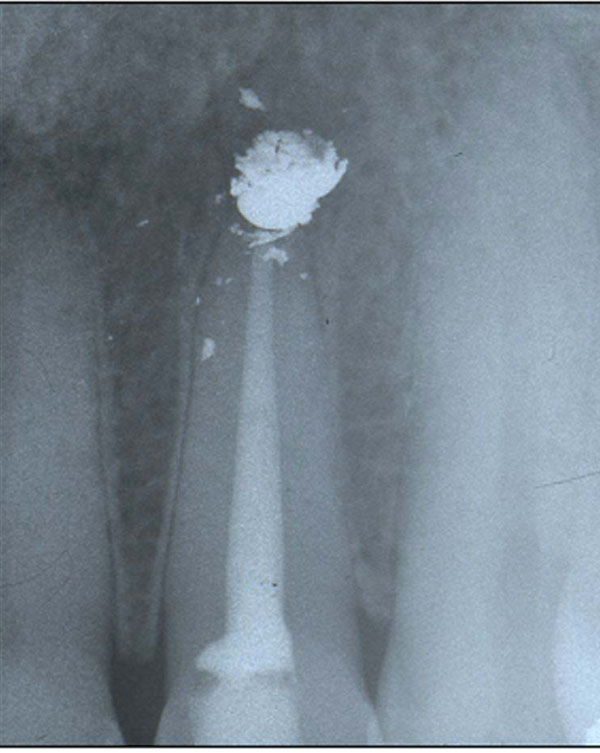

Xrays of overextended root filling on tooth 46 before and after Overextension Of Endodontic Filling Material In Patients With Neurologic Complications Accidental overextension of endodontic filling material in patients with neurologic complications: Accidental overextension of endodontic filling material in patients with neurologic complications: In this case series, seven patients who complained of neurologic complication after overextension of canal filling material during endodontic treatment were presented. In this case series, seven patients who complained of neurologic complication after overextension of canal filling. Overextension Of Endodontic Filling Material In Patients With Neurologic Complications.

Endodontic treatment 2.2. (a) Periapical Xray endodontic overfilling Overextension Of Endodontic Filling Material In Patients With Neurologic Complications Accidental overextension of endodontic filling material in patients with neurologic complications: Accidental overextension of filling material during endodontic treatment may cause mechanical and chemical irritation of the adjacent tissue. Complications post routine endodontics may be due to overextension of endodontic filling which may have mechanical and/or chemical mode of. In this case series, seven patients who complained of neurologic complication. Overextension Of Endodontic Filling Material In Patients With Neurologic Complications.